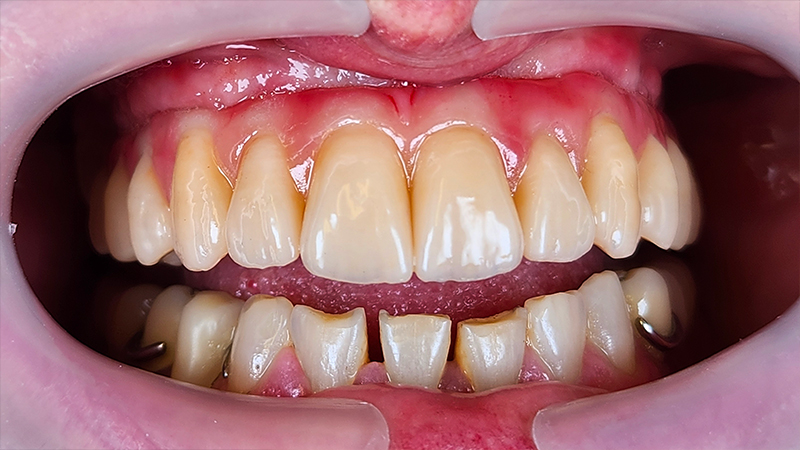

Situazione clinica iniziale

Fig. 1

protesi provvisoria a carico immediato dopo l'integrazione degli impianti

Fig. 2

Effettivamente, il provvisorio è molto piacevole. Le resine da stampa 3D e i moderni compositi stanno cambiando il nostro approccio alla produzione dei dispositivi protesici, ma avevamo bisogno di una sottostruttura che garantisse una durata adeguata per la protesi, mirata a sopravvivere oltre i 15-20 anni della vite utile di un impianto dentale.